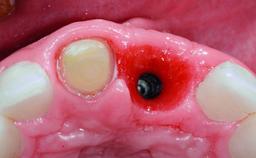

A 30-year-old patient presented at our clinic with a chief complaint of pain in her endodontically treated right maxillary central incisor (tooth 11) with a post-and-core and a fixed single crown. She had a very high lip line, a medium to thin soft-tissue phenotype, and a medium scalloped gingival contour. She also had high esthetic expectations because of her young age and beautiful smile. However, her expectations were realistic and she understood the risks of the treatment. At the initial clinical examination there was a slight mobility of tooth 11; no fistula was observed. The patient also had a single crown on the adjacent tooth 21. Both restorations were old and esthetically deficient. A digital periapical radiograph showed a very small periapical radiolucency, a thick intraradicular post, and no separation between root fragments.

Bone Augmentation Staged

Augmentation Materials Xenogenous|Membrane

Soft Tissue Grafting Simultaneous